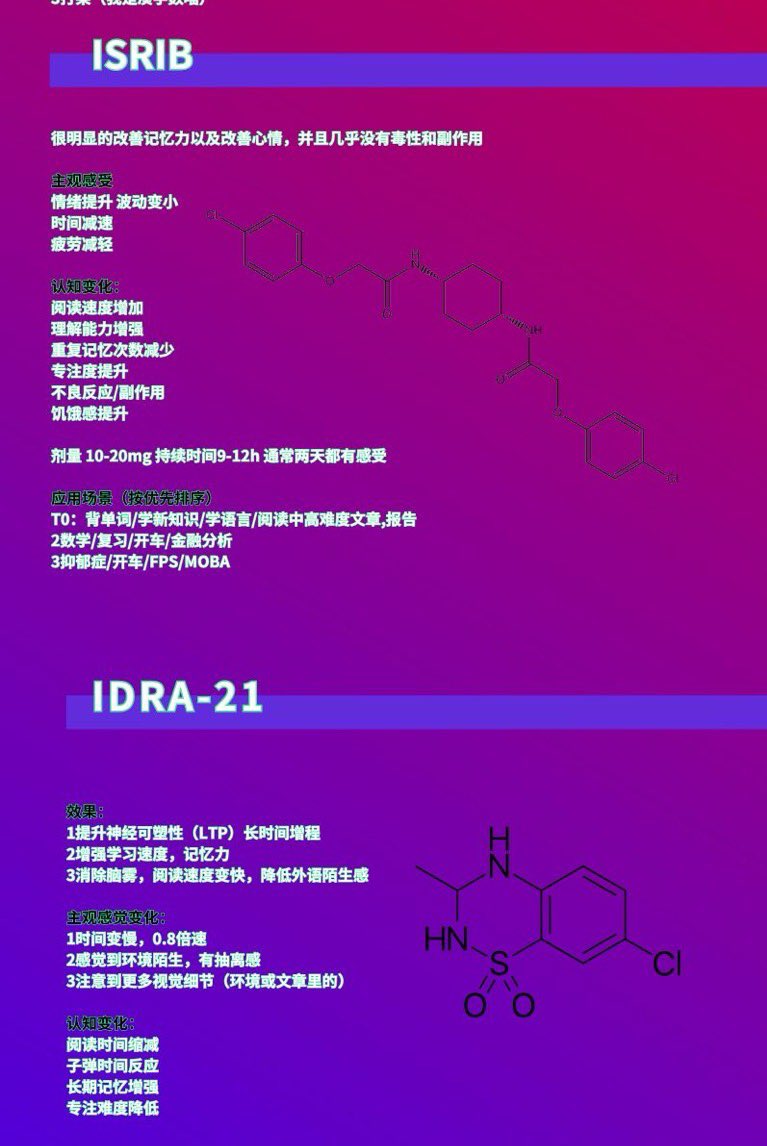

关于后藤提到过的“反解离”

首先,从定义上讲,“反解离(anti-dissociative)”并不是一个标准的医学术语或者广泛认同的药理学分类。在正规资料,比如医学文献、维基百科、精神药理学教科书中,目前并没有“反解离药物”这个正式概念。

看上去像是为了描述某类特定效应而创造的术语(可能是nmda受体活性增强),用来对抗因NMDA受体拮抗剂(比如氯胺酮、DXM、PCP等)引发的解离体验(dissociation)。

那么更常见的是将其归入认知增强剂(cognitive enhancers),特别是改善认知连接性(connectivity)和现实感知(reality testing)的类型。

但其实在药理学上,单纯用“受体激动剂”来逆转“受体拮抗剂”的效应,有时会导致过度激活。

对于NMDA受体而言,过强的NMDA活化本身就与兴奋性毒性(excitotoxicity)和精神病样症状(psychotomimetic effects)有关,比如谷氨酸风暴可以引发严重的焦虑、妄想、乃至癫痫。

也就是说,简单地“激动-解除拮抗”在中枢神经系统是很危险的做法,尤其是对于易感个体(如有精神分裂素质的人)。

科学的处理方式一般是通过更细致的调节,比如微调NMDA/AMPA平衡、调节其他辅助途径(如GABA、5-HT、mGluR受体),而不是简单粗暴地用“NMDA增强剂”去顶回去。